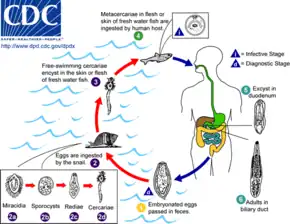

Below are some life cycles of fish parasites that can infect humans:

Life cycle of the liver fluke Clonorchis sinensis

Life cycle of the liver fluke Clonorchis sinensis Life cycle of the parasitic Anisakis worm

Life cycle of the parasitic Anisakis worm Life cycle of the fish tapeworm Diphyllobothrium latum

Life cycle of the fish tapeworm Diphyllobothrium latum Life cycle of the digenean Metagonimus, an intestinal fluke

Life cycle of the digenean Metagonimus, an intestinal fluke